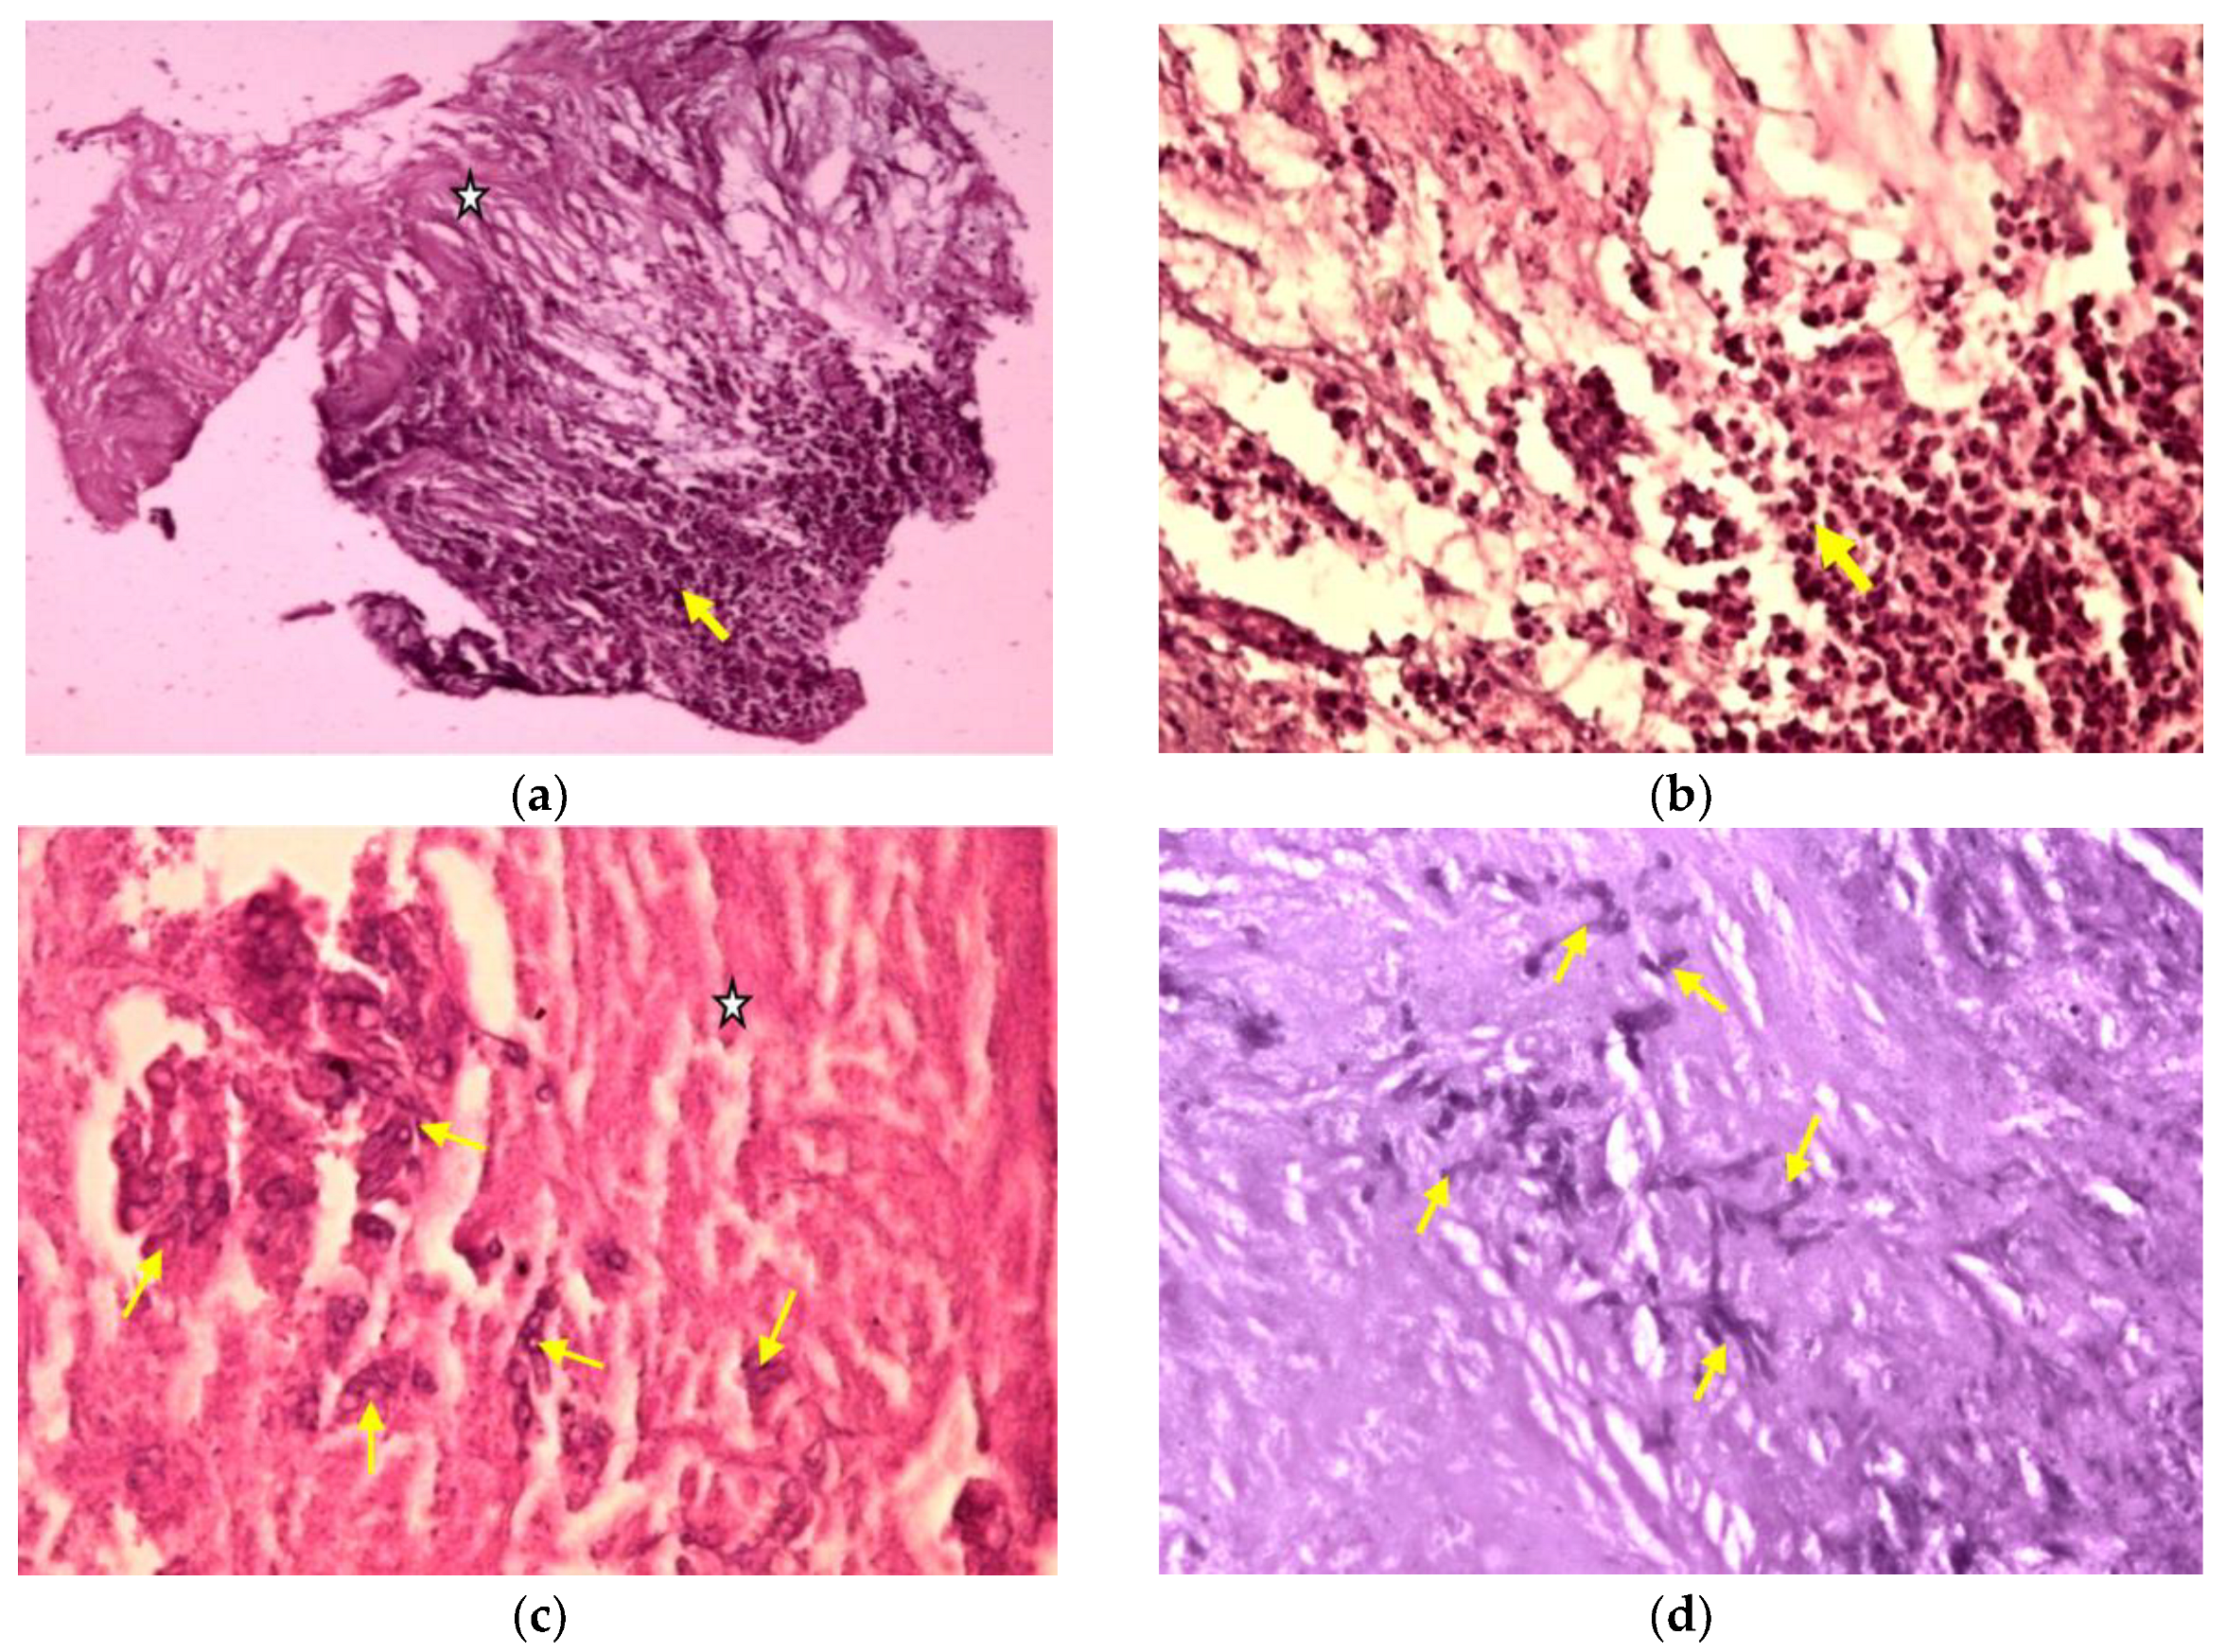

- Gram-stained smears showed an intense inflammatory reaction with neutrophils;

- Twenty colonies of Aspergillus spp. were identified in fungal culture.

- Mycological demonstration of Aspergillus fumigates hyphae by microscopy from spu-tum, microscopy and culture from bronchial aspirate, and histopathological evi-dence of the presence of Aspergillus fumigates hyphae with dichotomous branching in the spinal cord biopsy;